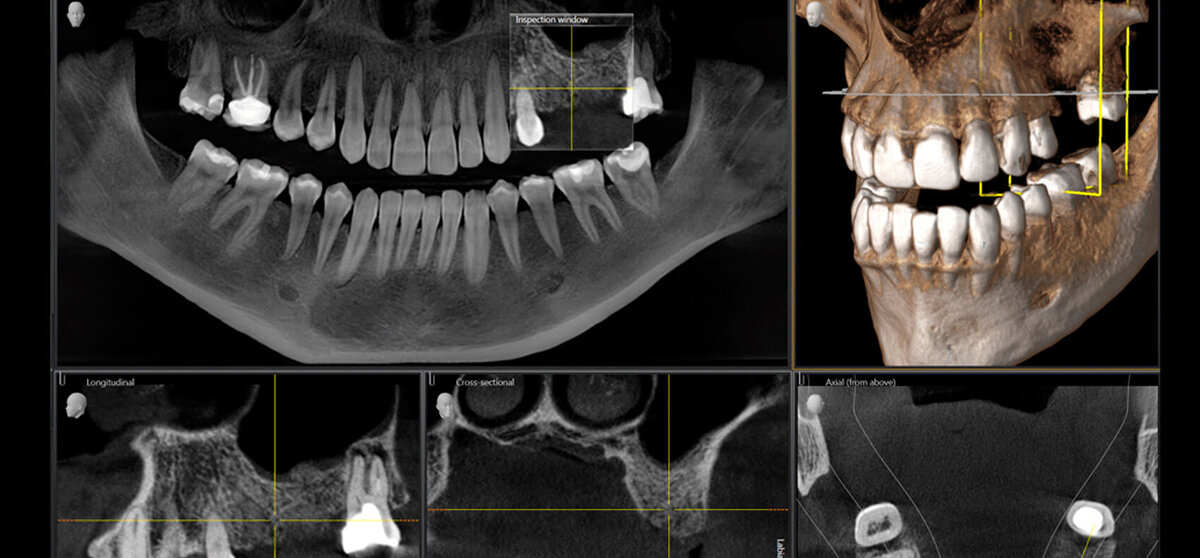

1. Подготовка пациента. Перед проведением процедуры проводятся все необходимые обследования и анализы, в том числе и компьютерная томография. С помощью полученного 3D снимка врач изучает строение корня, а также состояние и объем костной ткани.

КТ-исследование